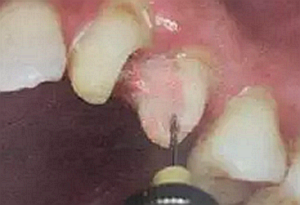

纖維樁修復(fù)之精細(xì)操作

(鑷子夾持(正確))

(污染手套夾持(錯(cuò)誤))

(技工鉗裁剪(錯(cuò)誤))

試放后應(yīng)按所需長度用細(xì)粒金剛砂車針切割裁剪。